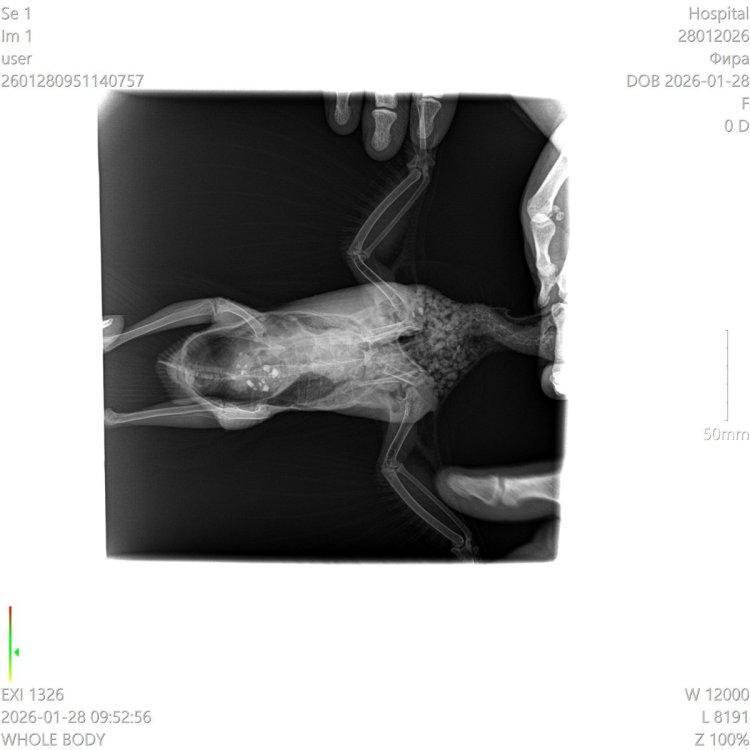

Сегодня сделади рентген. Сдали анализы, какие смогли: на кокцидий- отрицательно, на другие глисты - пока ждем, бакпосев помета и смыва с горла - будут говы или в конце этой неделе либо до следущей среды.